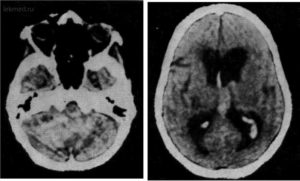

Диагностика мозжечкового поражения

Составить полную клиническую картину заболевания можно только в стационаре. Доктор собирает анамнез, назначает МРТ или КТ головного мозга для выявления очагов поражения. Пациент сдает анализы и проходит ЭКГ. Диагностика позволяет установить тип инсульта и подобрать оптимальные методы лечения.

В настоящий момент оснащение лечебных заведений позволяет без труда и в кратчайшие сроки диагностировать венозную ангиому еще на ранней стадии развития и начиная с малых размеров.

Наиболее достоверными считаются результаты исследования, сделанные при помощи ангиографии — рентгеновского метода исследования проходимость сосудов головного мозга с применением контрастного вещества.

На полученном таким образом снимке будет четко видно место локализации опухоли, размер, что позволит переделить характер новообразования и его влияние на окружающие ткани.

Также к не инвазивным методам исследования структур мозгового вещества и его кровеносных сосудов относится КТ и МРТ головного мозга с введением контрастного вещества.

Эти методы позволяет получить достаточное количество послойных снимков головы в нескольких проекциях, что позволяет выявлять малейшие признаки патологии.